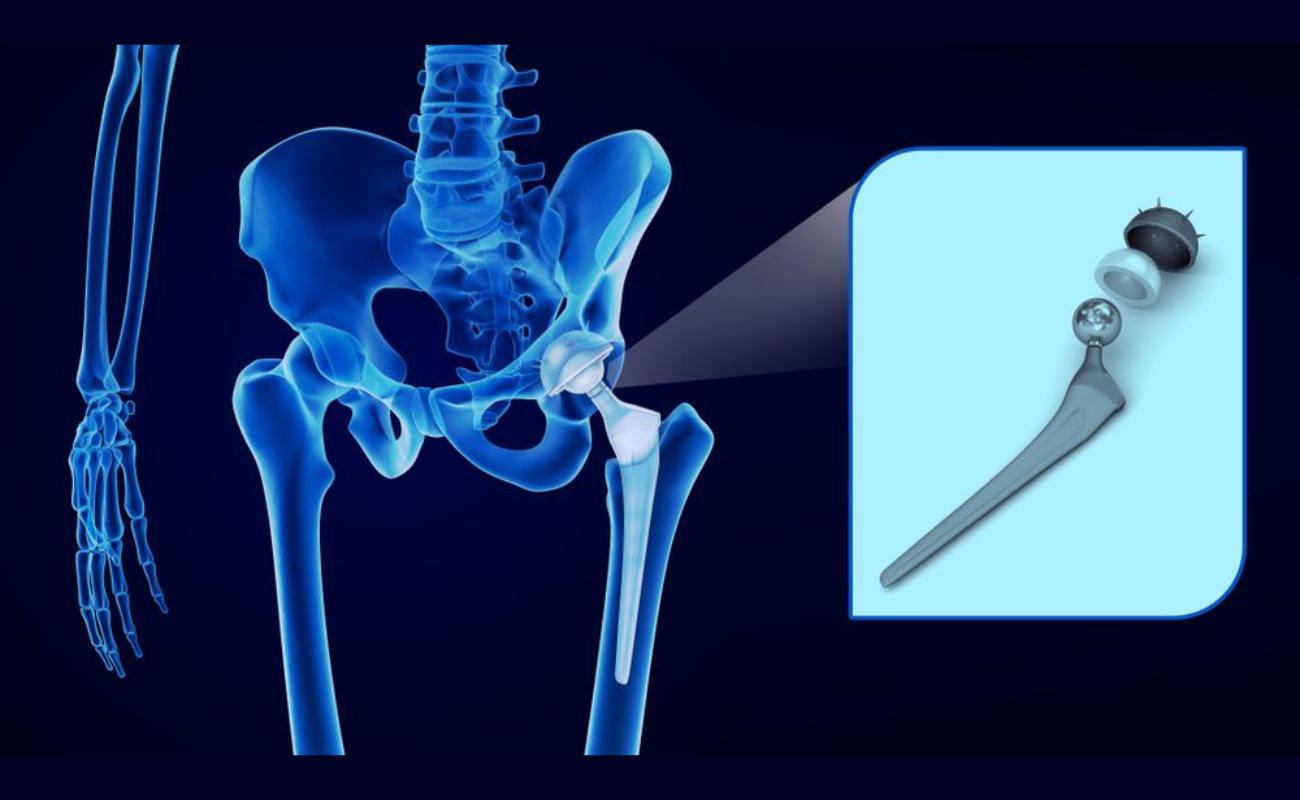

Osteoarthritis

Osteoarthritis leads to loss of cartilage when rate of cartilage damage exceeds the rate of repair. Cartilage is necessary to prevent bones from rubbing against each other. When the cartilage cover is lost, the bones come into contact and result in painful movement.

Can Surgery Remove Arthritis?

Arthritis is a chronic condition that causes inflammation, swelling, and pain in the joints. It can be debilitating, making it difficult to perform day-to-day activities such as walking or writing. Fortunately, for those who are suffering from this condition,

Knee osteoarthritis is a common condition characterized by the gradual deterioration of cartilage in the knee joint. It can cause pain, stiffness, swelling, and reduced mobility,

Preventing Arthritis with Effective Weight Management

Arthritis, a debilitating condition characterized by joint pain, stiffness, and swelling, affects millions of people globally. While aging and genetics are key contributors,